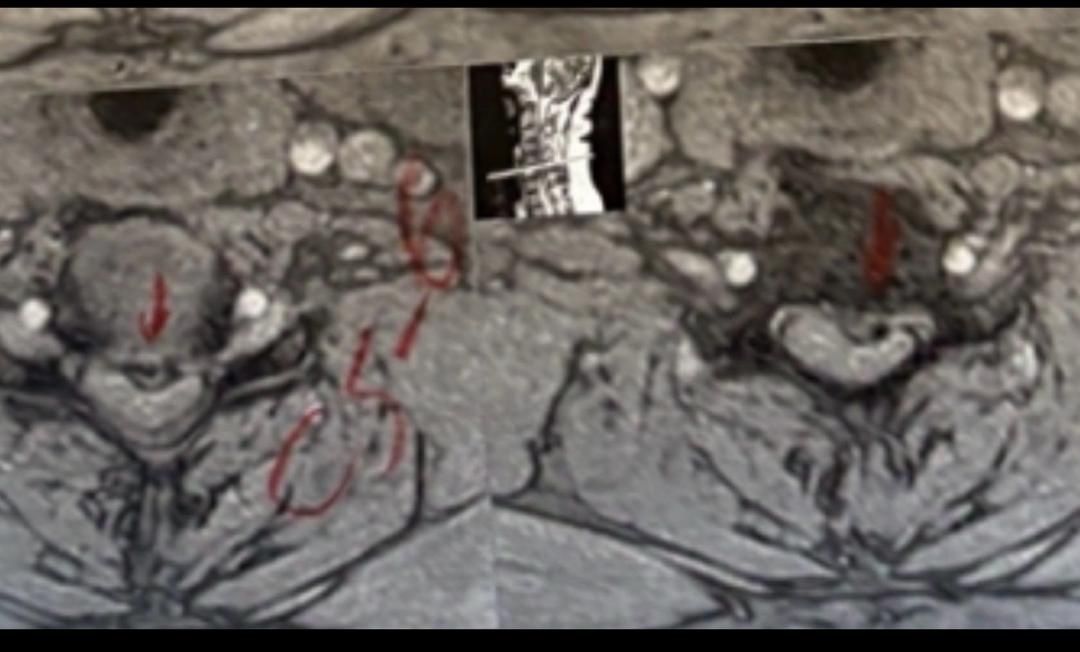

41 years old man presented to my clinic in October 2023 with acute and sever R neck pain with radicular pain to his R upper extremity along C6 dematom since 2 weeks ago. Examination didn’t show any upper motor signs. Was suggested urgent surgery

I ordered EMG/ NCV : showed mild R C6, C7 irritation without any active axonal loss

In his MRI was reported R. para R. IVF Massive extrusion. I decided to control his pain and manage this patient with reevaluation of patient every other session. For 5 sessions i just used acupuncture and laser and IFC and mild adjustments to his R. T3-T7 and mild arthosteem to above and below involved segment. Cervical adjustment considered contraindicated for this patient. From session 6th- 8th i started to use mild/gentle cervical decompression. He used soft cervical collar all the time. His pain decreased by 80 percent

I gave him cervical traction pump to be used 3-5 times per day at home for the next 3 months and i released the patient. He was evaluated every week once for one month and after that every 2 weeks. After 3 month I repeated MRI. Size of the herniated disc was reduced greater than 50 percent. Asked him to do another mri in 6 months

In general: Precise selection of the patients, examination,diagnosis, plan of management, reevaluation and treatment can be done by doctors of chiropractic for the patients with spinal disc herniation and stenosis Moreover giving reasonable time to these kind of patients under direct supervision by their chiropractic doctors can prevent unnecessary surgery. Proper selection of these kind of patients is another important fact that can be done precisely by chiropractors.

MRIs before and after proper management of this patient: